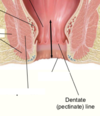

What are the two sections of the perineum (anterior and posterior)?

Urogenital triangle and anal triangle.